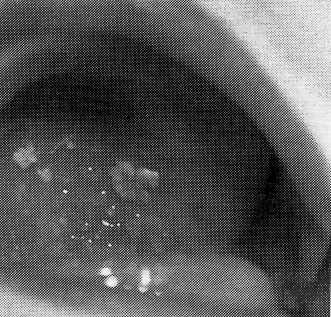

Кандидоз мочевыделителъной системы. Кандидозный уретрит и цистит характеризуются учащенными болезненными мочеиспусканиями, помутнением мочи, иногда с примесью крови, выделениями из уретры беловато-сероватого цвета и повторными выявлениями в моче дрожжепо-добных грибов. При цистоскопии на стенках мочевого пузыря обнаруживаются творожистые наложения, соскоб из которых представляет скопление почкующихся клеток и псевдомицелия гриба.